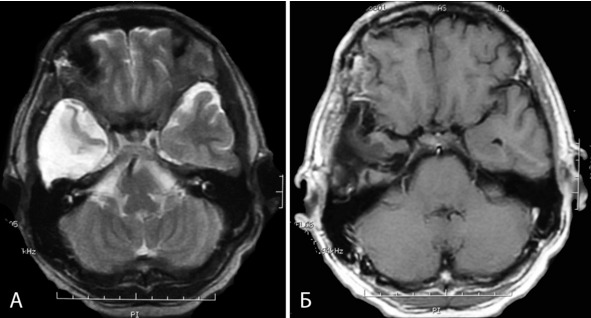

Чемпионка России по академической гребле в юношеской группе. В 2002г появилась интенсивная головная боль, снизилось зрение. Лечилась по месту жительства, КТ, МРТ не производились, выписаны очки. Через 2 месяца зрение восстановилось. В марте 2006г появились легкие нарушения статики и походки. В августе 2006г вновь появилась головная боль и ухудшение зрения. Лечилась с диагнозом «Вегето-сосудистая дистония». 4.09.06 упала на улице, сознания не теряла. 12.09.06 выполнена КТ головы, при которой выявлены множественные объемные образования мозга, выраженная гидроцефалия с перивентрикулярным отеком. Направлена в институт, где при МРТ 25.09.06 выявлены множественные каверномы головного мозга: кавернома правой ножки мозга и таламуса с распространением в III желудочек и частичной окклюзией сильвиева водопровода, признаками кровоизлияния; небольшие каверномы правой лобной доли и левой височной доли (рисунок 24: А, Б, В). При обследовании родственников каверномы также выявлены у отца и дочери пациентки (рисунок 24: Д). 3.10.06 больная госпитализирована в институт. Неврологический статус при поступлении: выраженная общемозговая симптоматика в виде сильной головной боли, заторможенности; мезенцефальные симптомы, экстрапирамидные симптомы в правых конечностях, выраженные нарушения статики и походки.

Учитывая тот факт, что ведущими в клинической картине являются симптомы окклюзионной гидроцефалии, а удаление каверномы среднего мозга и таламуса сопряжено с высоким риском нарастания очаговой симптоматики, 10.10.06 выполнена перфорация дна III желудочка. В ходе операции через эндоскоп была хорошо видна субэпендимальная кавернома (рисунок 24, Г). В послеоперационном периоде отмечен постепенный регресс общемозговых симптомов.

Рисунок 24. А, Б, В – МРТ б-ной К. Диагноз: множественные каверномы (3) головного мозга. А – кавернома полюса правой лобной доли (режим Т2, аксиальная проекция). Б – кавернома ножки мозга и таламуса, окклюзионная гидроцефалия (режим Т1, аксиальная проекция). В – кавернома левой височной доли. Виден также фрагмент каверномы среднего мозга справа (режим Т2, аксиальная проекция). Г – кавернома среднего мозга, вид на эндоскопической операции (премоторный доступ слева): 1 —субэпендимальный фрагмент каверномы в проекции водопровода мозга, 2 – таламусы, 3 – левая гипоталамическая борозда, 4 – эпиталамическая спайка, 5 – межталамическое сращение. Д – МРТ отца больной: субкортикальная кавернома правой височной доли (режим Т2, аксиальная проекция). Катамнез: периодически обращается в институт для контрольного обследования, последнее обращение – 21.09.10. Состояние стабильное, ведет активный образ жизни. Сохраняется мягкая мезенцефальная симптоматика. МРТ – без динамики. Случай демонстрирует возможность успешного лечения связанной с каверномой окклюзионной водянки, путем выполнения шунтирующей операции.